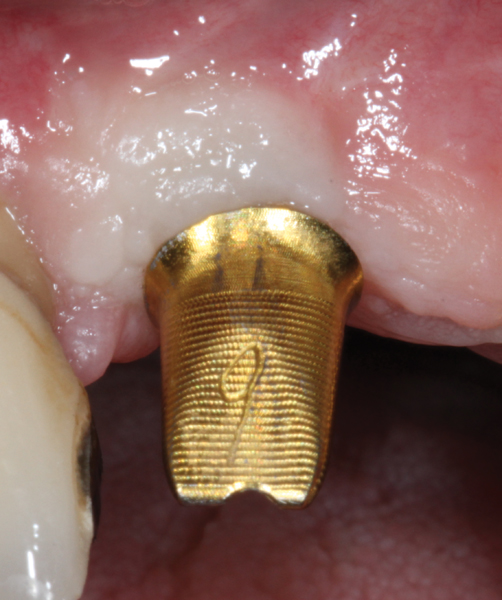

Fig 8. Some implant abutments flare drastically at the connection with the implant. This will compromise blood supply to the area, encroach on the peri-implant biologic width, and likely result in a more apical position of the bone and soft tissue. This design should be modified for use in the esthetic zone.

Figure 8

Fig 9. The flared area is recontoured to a diameter no bigger than that of the implant. This is done preoperatively with a heatless stone wheel and then polished.

Figure 9

The narrowed abutment emergence profile will minimize encroachment on the peri-implant

bone. This design will help to preserve the peri-implant tissue and may enhance the final outcome.

Abutment selection for the provisional restoration must meet three key criteria: biocompatibility, high strength, and narrow. Though variation exists between systems, a narrow-diameter titanium abutment is generally available and easily meets the above criteria. When implemented in immediate load cases, strength of the abutment is critical to avoid having to manipulate components at the head of the implant during the period of low implant stability. Some provisional abutments are designed with a flared collar at the interface that can be removed (Figure 8 and Figure 9) to enhance the potential soft-tissue volume during healing.18 The length of the abutment will need to be shortened to fit within the tooth shell. Any adjustments to the abutment are to be done outside the mouth to avoid titanium debris in the wound and transfer of heat and vibration to the implant. It is esthetically beneficial to opaque the surface of the abutment with a low-viscosity opaquing resin. This will help to minimize any graying of the provisional.